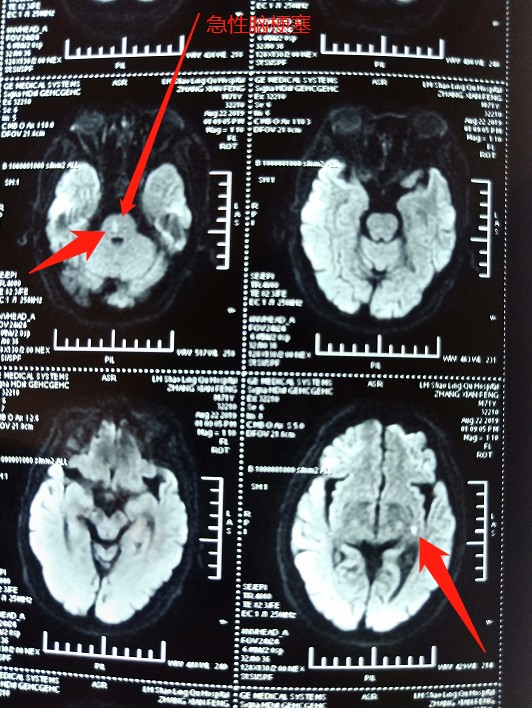

核磁共振可见急性脑梗死。